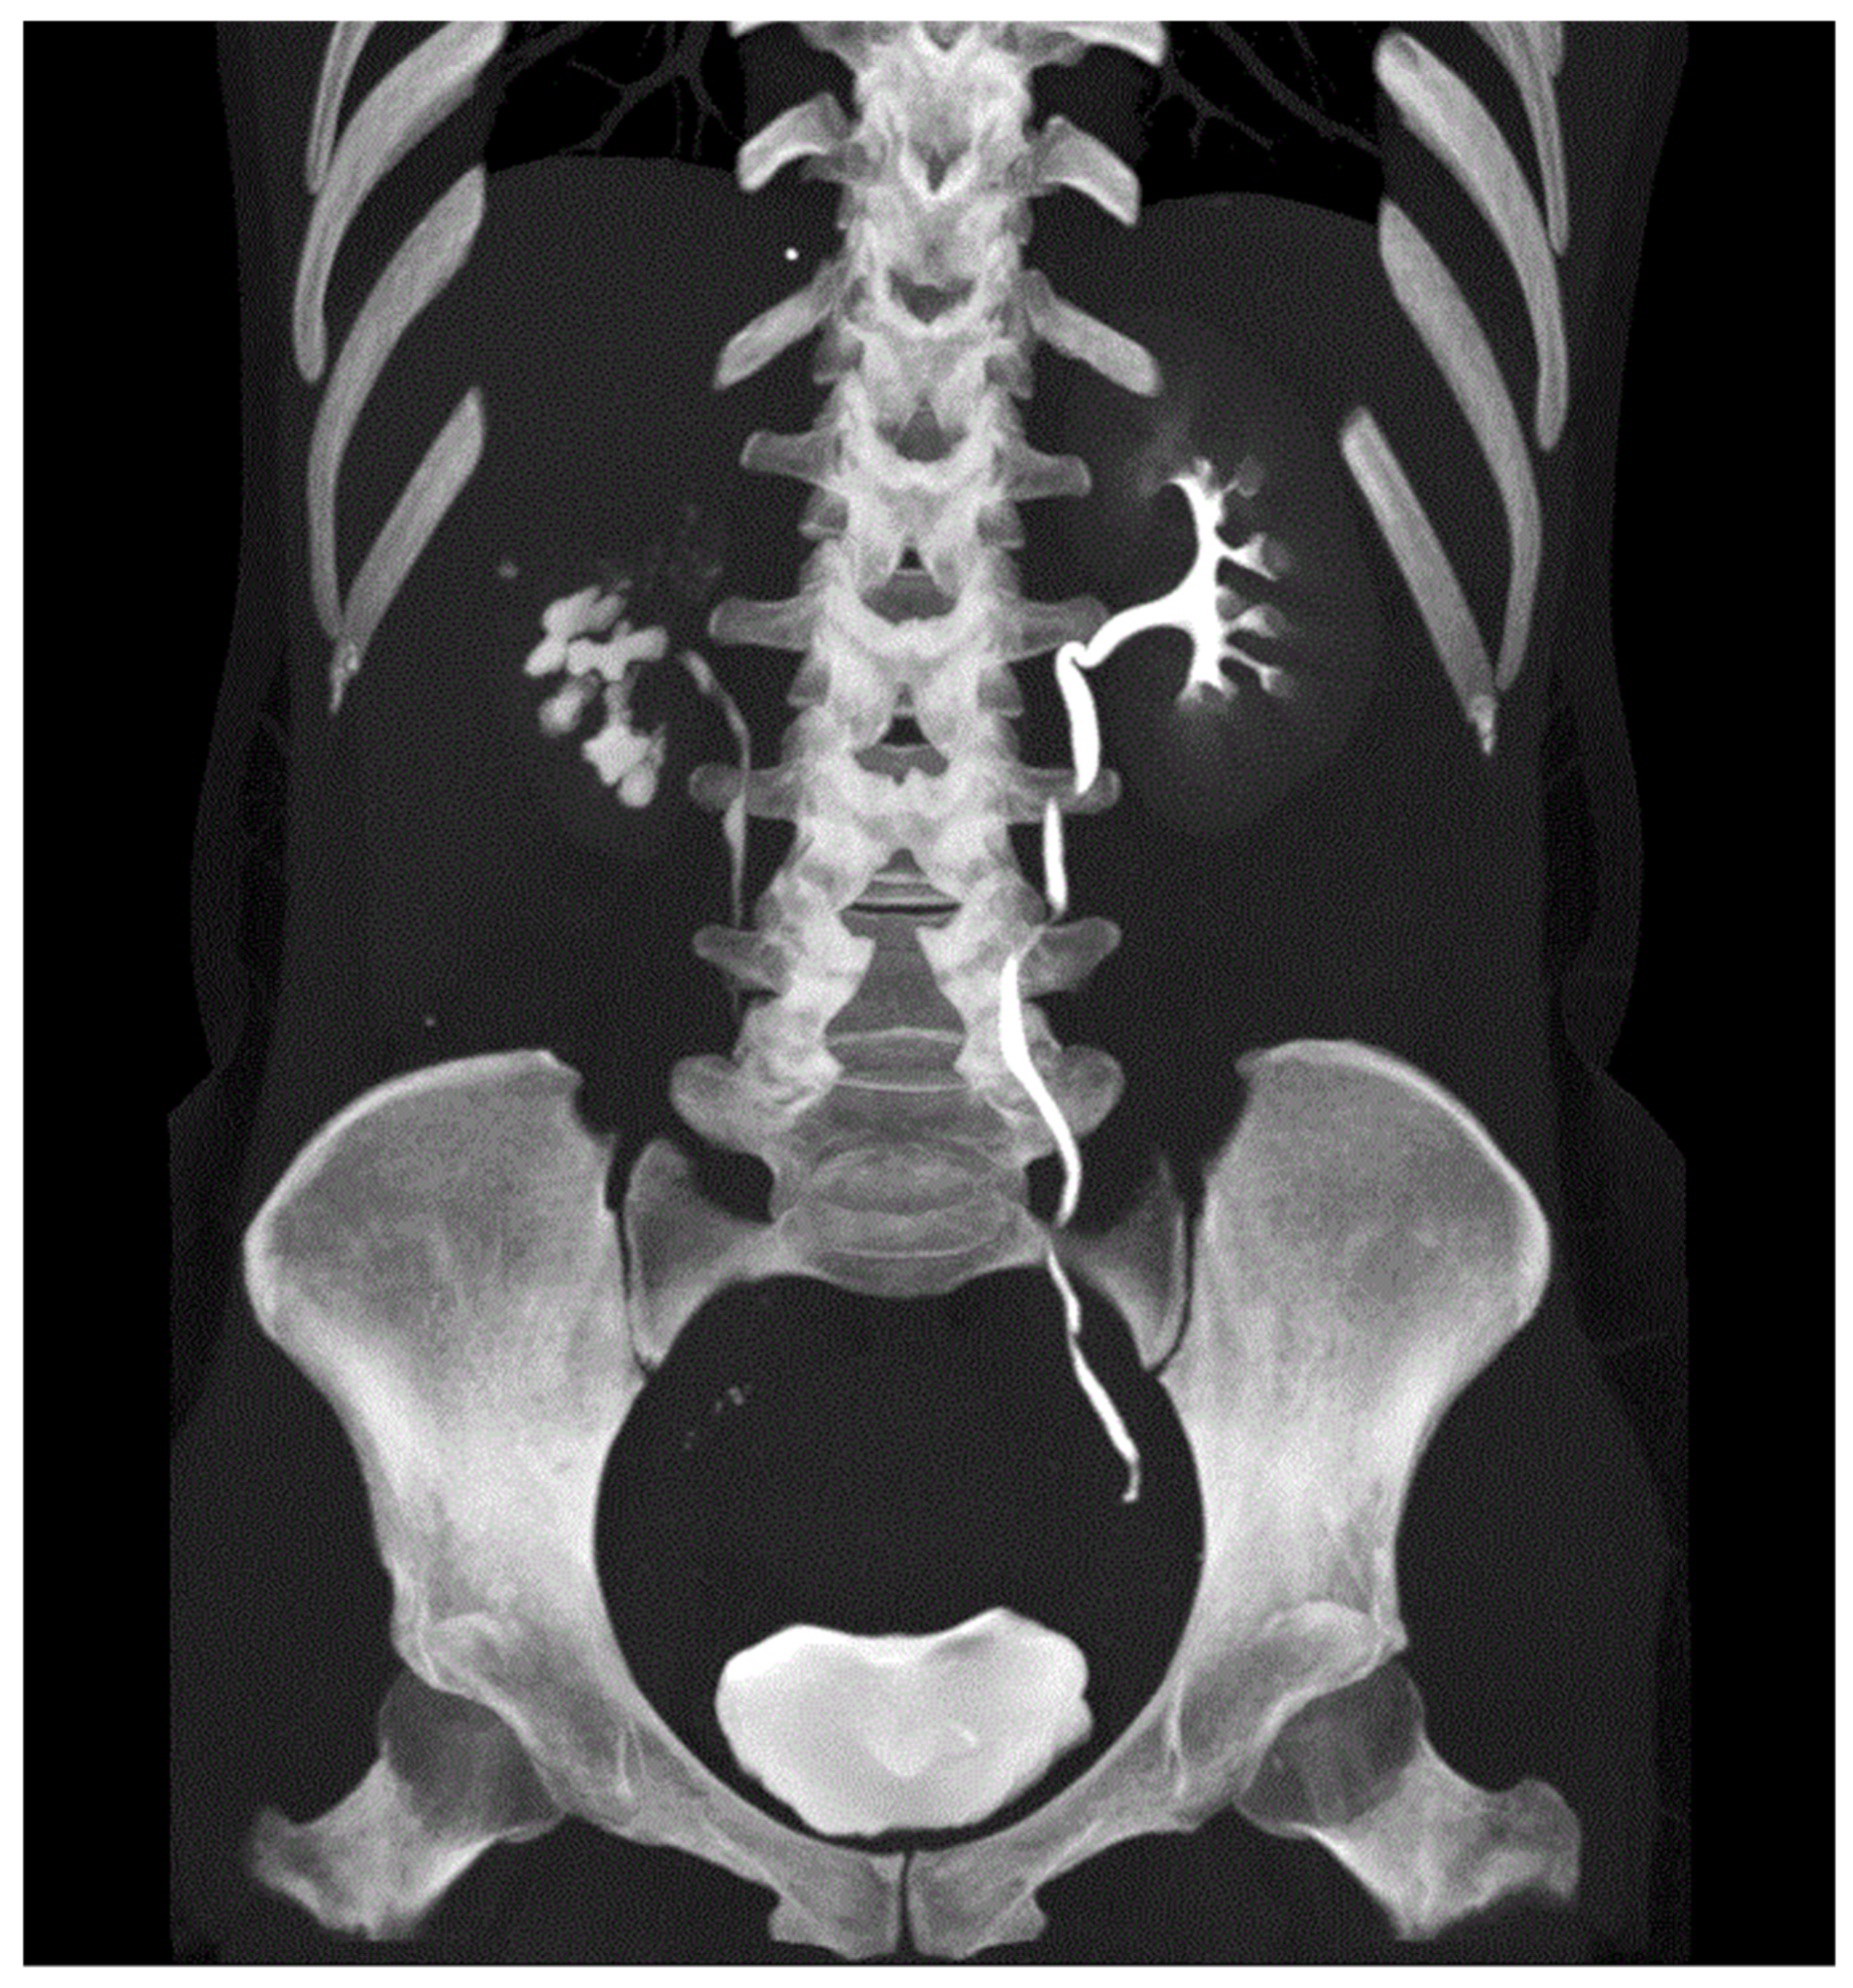

CT Scan and CT Urography

- Wang, L.-J.; Wu, C.-F.; Wong, Y.-C.; Chuang, C.K.; Chu, S.-H.; Chen, C.-J. Imaging findings of urinary tuberculosis on excretory urography and computerized tomography. J. Urol. 2003, 169, 524–528. [Google Scholar] [CrossRef]

- Prakash, J.; Goel, A.; Sankhwar, S.; Singh, B.P. Extensive renal and ureteral calcification due to tuberculosis: Rare images for an uncommon condition. BMJ Case Rep. 2013, 2013, 2012008508. [Google Scholar] [CrossRef]